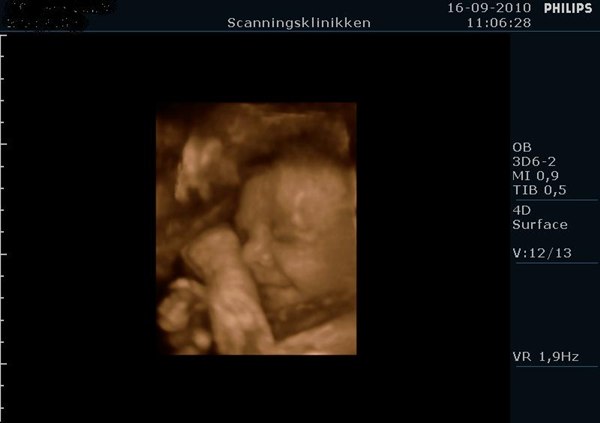

Det så bare så skægt ud med den hikke, og tror nok det kom med på dvden i starten hvor hun lavede 2D...

Men ja, hun ser bare så dejlig ud, og vil bare så gerne have hende ud med det samme, men hun skal jo lige blive lidt længere alligevel

Ej hvor sjovt, smiler.. Det er da ret specielt at have på dvd

Hehe.. ja, efter sådan en 3D/4D har man bare lyst til at føde og få den lille ud i sine arme